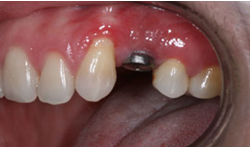

![]() |

| Mất 1 răng |

Chụp phim Panorama kiểm tra

| Phim Panorama |

Dựa trên phim Panorama ta có thể thấy R24 bị tiêu xương ổ răng do mất răng lâu ngày

Kế hoạch điều trị: cấy 1 implant nâng đỡ R24, ghép xương